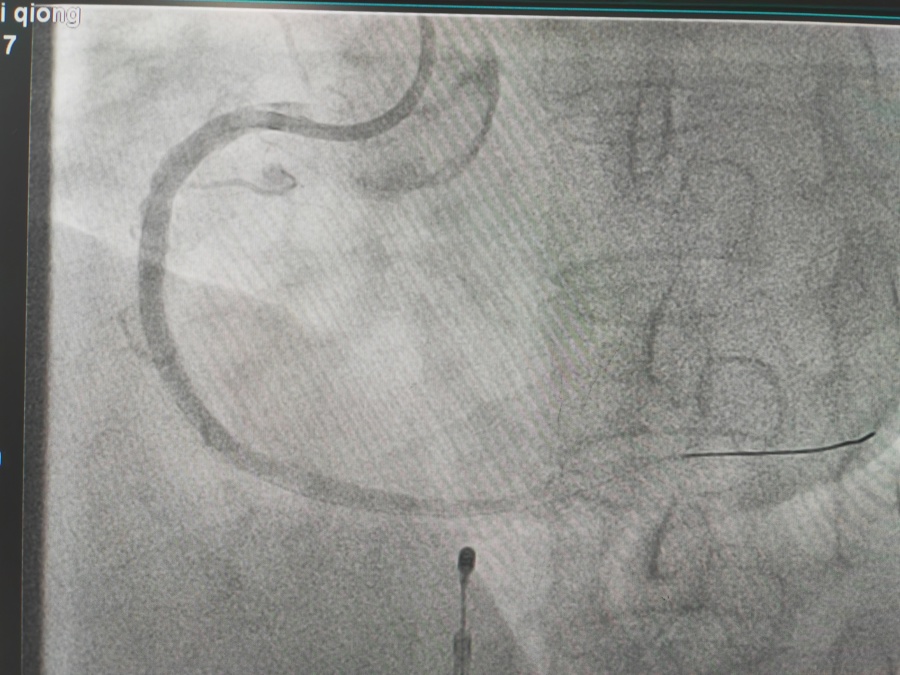

冠心病的治疗

冠脉支架置入术是将以不锈钢或合金材料刻制或绕制成管状而其管壁星网状带有间隙的支架(药物支架),置入冠状动脉内已经或未经PTCA扩张的狭容节段支撑血管壁,维持血流畅通。因球囊扩张后,约20-40%的病变会发生再狭窄,有些会发生急性冠脉闭塞而导致急性心肌梗死或死亡,所以在扩张后,多致需要再用冠脉内支架将病变处永久性撑开,即支架置入。置入支架是为了减少斑块撕袭后塌陷,急性塞,增加手术安全性,减少再狭窄。目前PTCA加上支架置入术已成为治疗冠心病的重要手段。